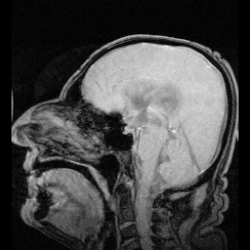

In neuroanatomy, the ventricular system is a set of four interconnected cavities known as cerebral ventricles in the brain.[1][2] Within each ventricle is a region of choroid plexus which produces the circulating cerebrospinal fluid (CSF). The ventricular system is continuous with the central canal of the spinal cord from the fourth ventricle,[3] allowing for the flow of CSF to circulate.[3][4]

The system comprises four ventricles:[5]

- lateral ventricles right and left (one for each hemisphere)

- third ventricle

- fourth ventricle

There are several foramina, openings acting as channels, that connect the ventricles. The interventricular foramina (also called the foramina of Monro) connect the lateral ventricles to the third ventricle through which the cerebrospinal fluid can flow.

The four cavities of the human brain are called ventricles.[6] The two largest are the lateral ventricles in the cerebrum, the third ventricle is in the diencephalon of the forebrain between the right and left thalamus, and the fourth ventricle is located at the back of the pons and upper half of the medulla oblongata of the hindbrain. The ventricles are concerned with the production and circulation of cerebrospinal fluid.[7]